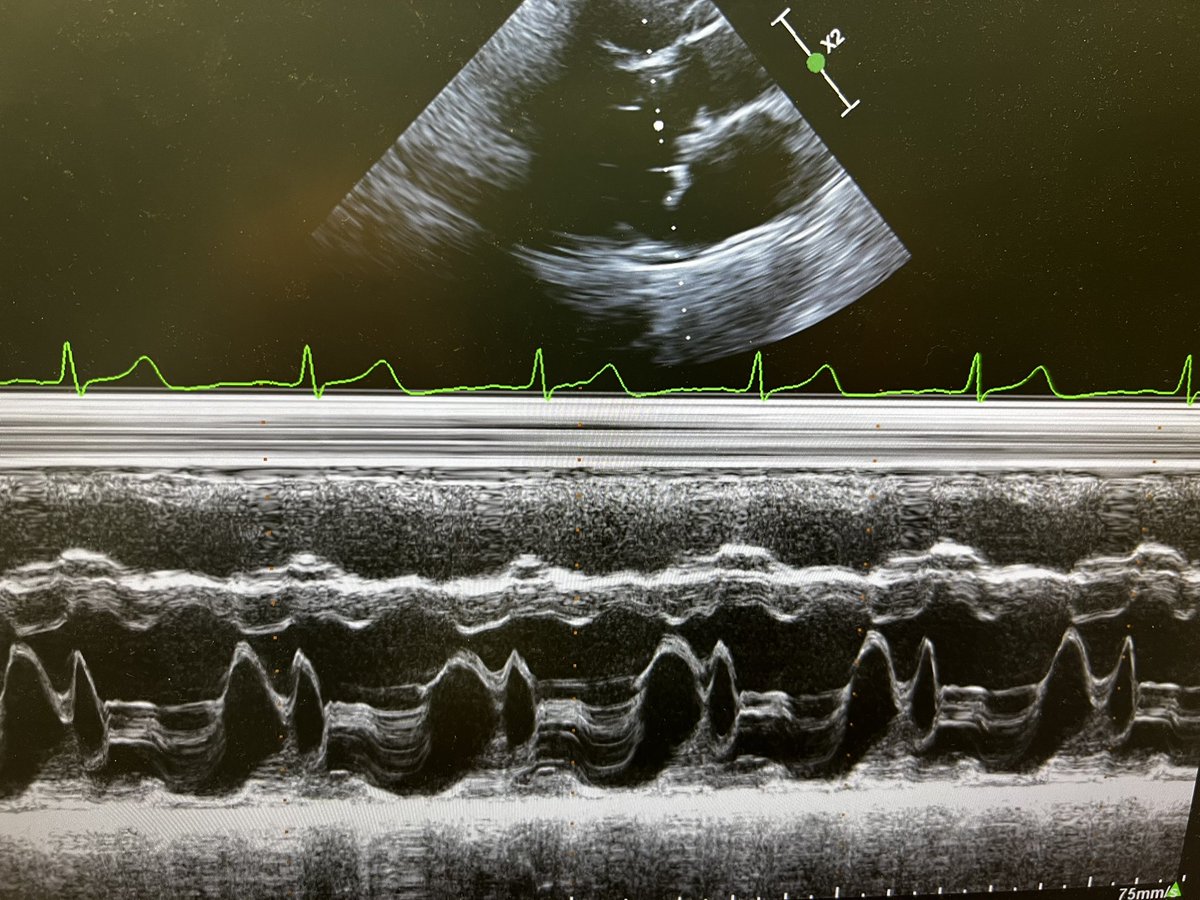

5/365 #firstecho #POCUS #VeXUS Left ventricular (LV) wall thickness and internal ∅ measures performed at end-diastole and end-systole 👇(PLAX)

Left ventricular (LV) wall thickness and internal

∅ measures performed at end-diastole and end-systole 👇(PLAX)